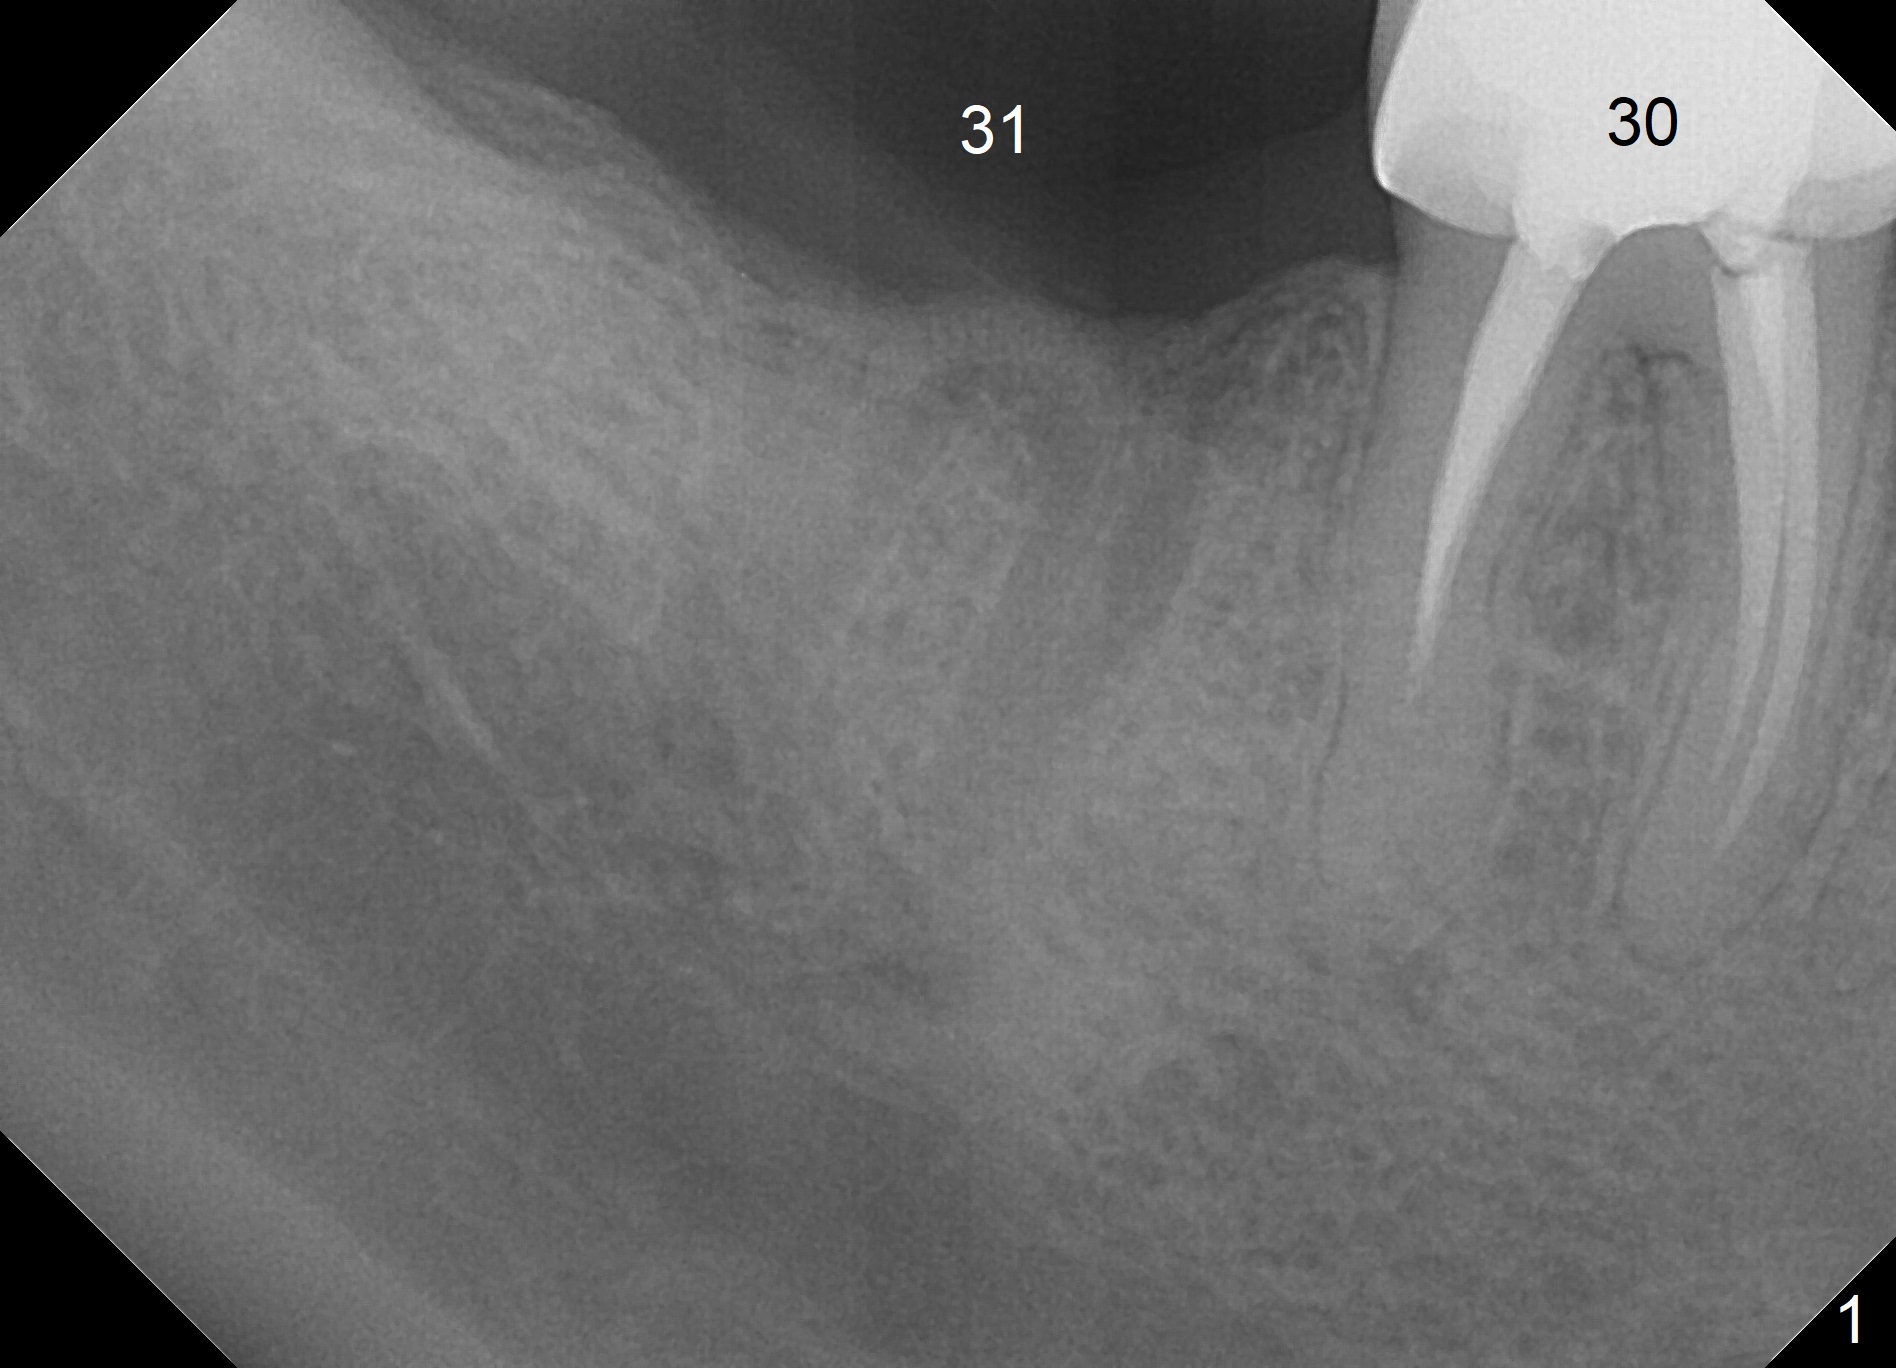

A 47-year-old man requests extraction of the tooth #30 for implant in spite of the fact of missing #31 (Fig.1), The tooth #30 remains symptomatic after RCT retreatment by a specialist. The apical distal canal is obliterated.